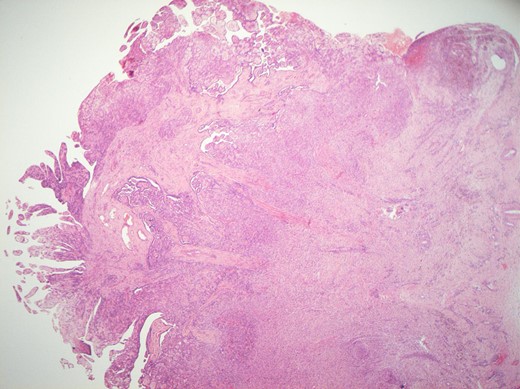

Histological features of the specimen were that of a fibrous cyst wall covered by cuboidal cells with bland nuclei (Fig. 1). Within the cystic space, there were branching, papillary structures with a fibrovascular core, lined with a single layer of bland cuboidal cells (Fig. 2). The stroma was oedematous and hyalinised. No sub-epithelial invasion was seen. There was no unequivocal cytologic atypia or atypical mitosis.

H&E staining of the specimen demonstrating a fibrous cyst wall covered by cuboidal cells with bland nuclei.

H&E staining of the specimen demonstrating branching, papillary structures with a fibrovascular core lined with a single layer of bland cuboidal cells.